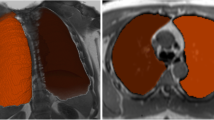

Figure 6 shows an example slice and corresponding segmentations with each tested method. Segmentation of mediastinal structures and peripheral lung portions was found to be the source of variation, leading to volume differences between software measurements. Semi-automated and fully automated methods showed similar segmentation errors, namely inclusion of nonlung tissue (i.e., mediastinum) and exclusion of lung tissue at low signal-to-noise regions (i.e., lung’s apices).

End-inspiratory segmentations

Semi-automated (ICC = 0.988–0.993) and fully automated segmentation results (ICC = 0.971–0.982) showed high agreement with MS (Tables 2 and 3). Results indicated that segmentations with GeoS, Pennati, and Ivanovska methods were similar to MS, with volume differences ranging from 0.59 to 1.37%. One subject was not segmented by Ivanovska’s method due to motion artifacts. 3D Slicer showed a significant difference (p < 0.001) with volume differences up to 2.89%. Bland–Altman plots showed good agreement between semi- and fully automated methods and MS (Fig. E5).